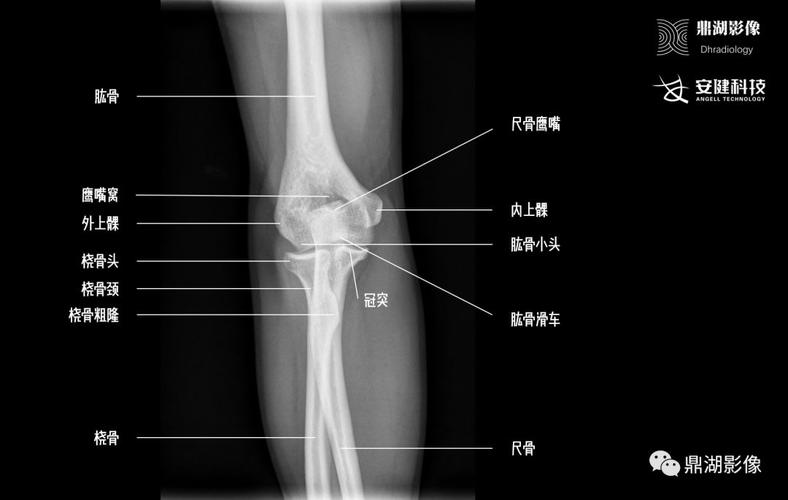

肘关节x线解剖

肘关节x线解剖及常见骨折诊断

正常肘关节x线解剖

2019--8-26 肘关节x线解剖学

肘关节侧位x线解剖

肘关节解剖